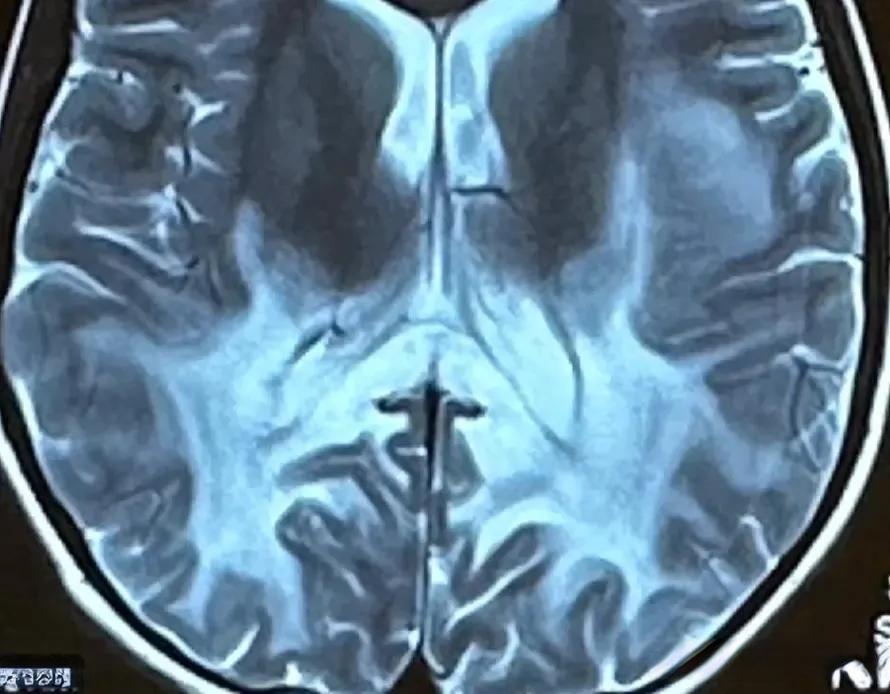

诊断ALD主要依赖于临床表现和一系列检查。血液检测发现VLCFA水平升高是诊断的关键指标,同时基因检测可以确认ABCD1基因突变。磁共振成像(MRI)可以显示脑白质的异常,特别是“蝶翼状”改变是ALD的特征性表现。此外,视力检查和皮肤活检也有助于诊断。